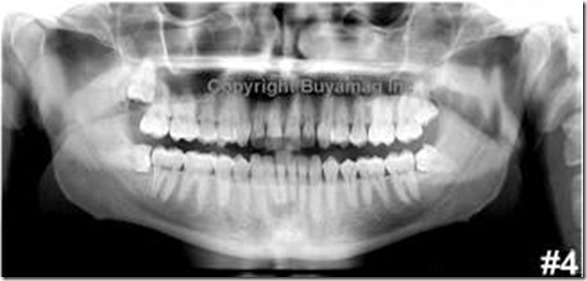

A clínica contava com o que de mais contemporâneo e atualizado pode se contar para atender aos pacientes que necessitam dos mais variados cuidados odontológicos, com uma equipe de profissionais habilitados para atender em japonês como em inglês. Com todas as informações do paciente, eles fizeram o primeiro exame que recomendava um novo raio-x, agora panorâmico, que fornecia a imagem completa da arcada dentária. O paciente tinha uma tela à sua frente com toda a imagem ampliada, onde o dentista explicava o que estava ocorrendo. Havia claramente uma bolsa de pus na retaguarda de um dos dentes, que com a pressão na viagem aérea procurava uma saída.

Exemplo de um raio-x panorâmico, mas o meu tinha uma qualidade de imagem bem superior

Isto provocava a infecção e a dor, que estavam aliviados pelas medicações anteriores, mas não recomendaria que o paciente utilizasse um transporte aéreo, pois o problema se repetiria. A recomendação era, mediante o uso de uma anestesia, se procedesse à extração de todo o pus possível, deixando até um canal para a eventual saída de um resíduo, ao mesmo tempo em que medicamentos anti-inflamatórios e anti-infecções fossem ministrados por alguns dias, até a avaliação da evolução do quadro.